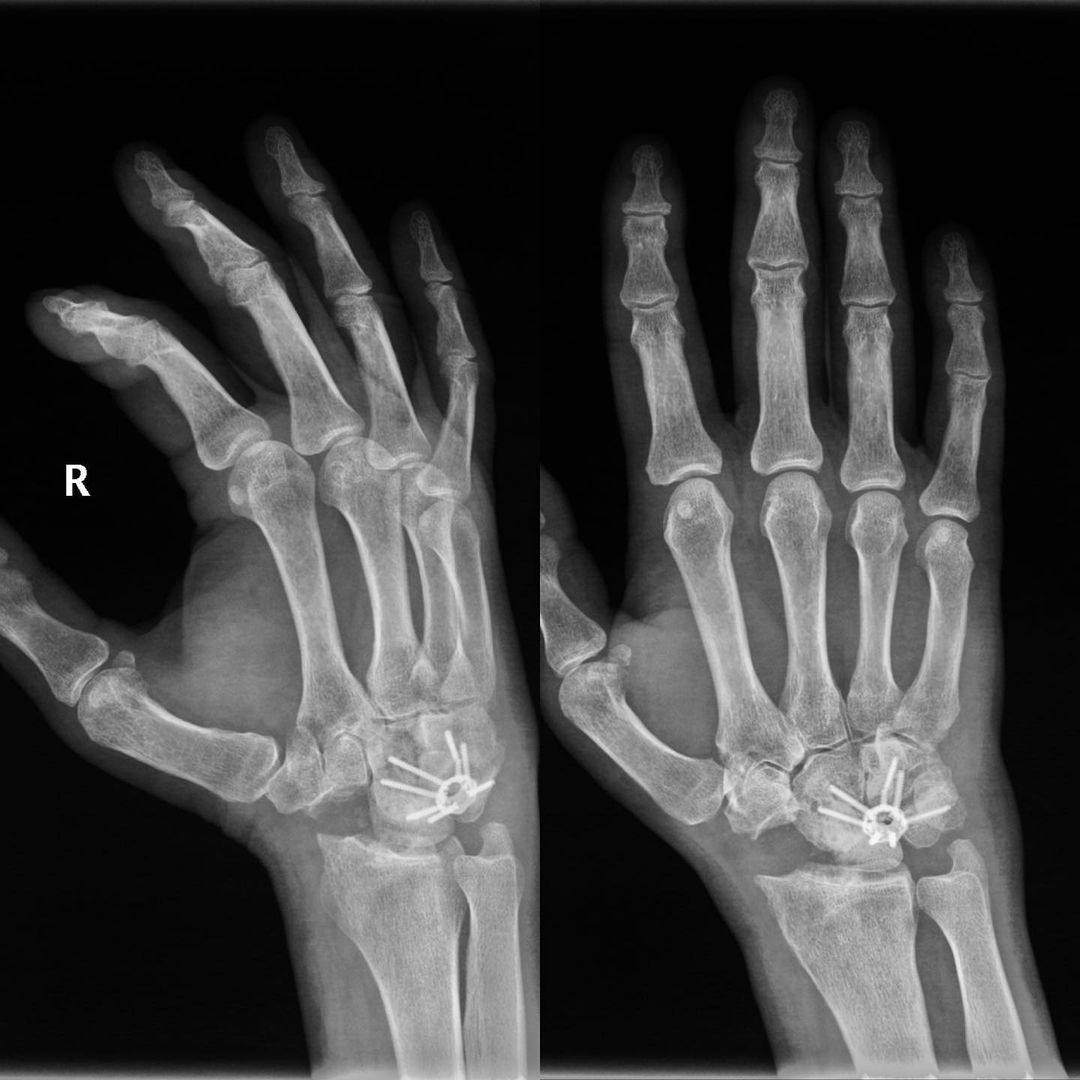

Для решения проблемы Гайк Каренович выполнил операцию – парциальный артродез.

Благодаря этому:

• Боли в руке резко уменьшились;

• Объем движений увеличился.

Пациент доволен результатом, качество его жизни значительно повысилось.

Но полностью восстановить функцию лучезапястного сустава через столько лет после травмы невозможно.